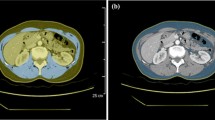

To assess measurement reproducibility, a strict method was used as follows. Reconstructed axial images with both a 1.25-mm and a 5-mm slice thickness were analysed using the software installed on the workstations of our radiology department (Suite-Estensa 1.9-Ebit-Esaote Group Company. 2015). The third lumbar vertebra (L3), at the level in which both transverse processes are clearly visible, was used as a bony landmark to properly identify the psoas muscle. Vertebrae were counted down from the cervical spine using scout images of the whole body or multiplanar reformatted (MPR) images from source thin-section axial images using the software on our workstations. In this study scout images were available for each patient. If there is no scout image of the whole spine or reformatted images, it is possible to identify the first lumbar vertebrae (L1) that is the first vertebra without a rib attachment. Once L1 has been found, the transverse processes can be used to count downward to L3. The psoas muscle was manually contoured bilaterally and the muscle mass was calculated as the cross-sectional area (square millimetres) (Fig. 1). The bilateral masses of the psoas were measured separately and the two values were averaged.

An example of measurement of psoas muscle total areas on axial CT image. The third lumbar vertebra (L3), at the level in which both transverse processes are clearly visible, was used as bony landmark to identify the psoas muscle area, contoured bilaterally (light blue area). Vertebrae were counted down from the cervical spine using scout images of the whole body or multiplanar reformatted (MPR) images from source thin-section axial images using the software on our workstations (not illustrated)